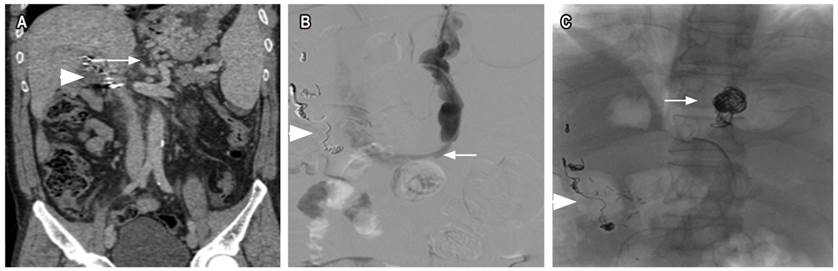

Segundo caso

Paciente masculino de 60 años con antecedente de cirugía de Puestow por neoplasia pancreática, quien asiste por melenas y anemia con hemoglobina de 7 g/dL. En la EVDA se observa sangre en la cavidad gástrica y un coagulo grande que no se remueve en la pared posterior de curvatura mayor del cuerpo proximal, de donde se observa sangrado en capa debajo de este; se realiza escleroterapia con solución de adrenalina y se realiza un control de esta. Además, se realiza una EVDA de control en la que se encuentran dos paquetes variciales grandes sin sangrado activo en el fondo del estómago, pero por el tamaño no es posible realizar una ligadura de estos, por lo que se requiere embolización. Se realiza una tomografía de abdomen en la que se encuentran várices tortuosas en curvatura menor del estómago (Figura 2A). Se realiza una venografía selectiva opacificando las várices tortuosas en una curvatura menor, un shunt gastrorrenal (Figura 2B), y una embolización con coils (Figura 2C) ocluyendo el flujo en las várices. El procedimiento se realizó sin complicaciones, y se dio de alta al día siguiente.